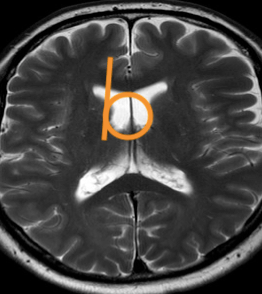

As a senior resident I reported an MRI of the brain of a patient with the cortex looking diffusely abnormal. There was a comparative scan, made 5 years earlier, briefly after the new 3T scanner had been set up in our hospital. This initial scan had been interpreted as normal by the professor in neuroradiology, a very knowledgeable doctor. Although the diffuse cortical abnormality was already visible, it was not recognised because inexperience with the 3T image.

Neuroradiology requires not only familiarity with the normal (MR) image but also understanding of the (patho)physiology. Whenever the physiology of the brain becomes too complicated for me, I go back in embryology to the neural tube, before the neurons and glial cells started to move and intertwine.

In Brain bit by bit vlogs I would like to share and show what I learned and know about different brain diseases, commenting on the radiological macroscopic picture and discussing what happened and happens at the microscopic, invisible cell level. Because this knowledge enables not only recognition of focal, obvious lesions in the brain but also diffuse, subtle disease that has just as much impact on life.

The patient turned out to have an iron metabolism disorder and the first scan was “pre” electroconvulsive therapy.